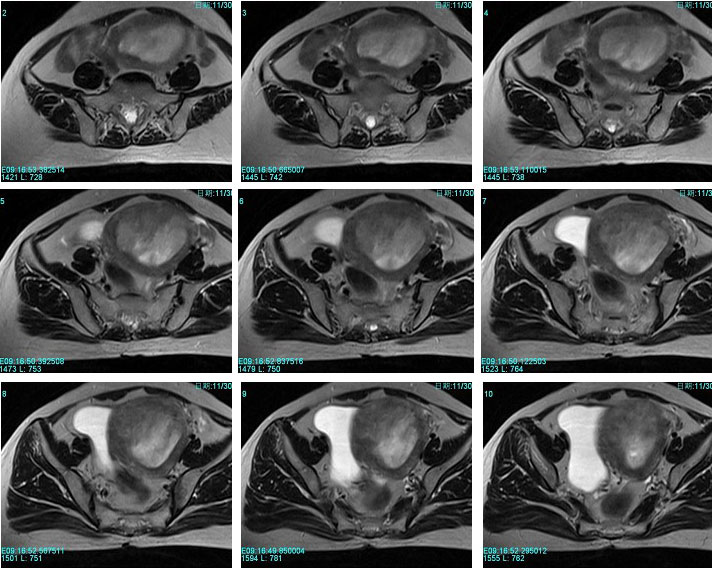

子宫恶性中胚叶混合瘤(癌肉瘤)

女性患者,52岁,月经量大,间断下腹痛一年余。多考虑:1:子宫前壁肌瘤。2:子宫内膜癌可能性大。已取活检,病理结果过几天出来。各位高手先讨论讨论。

子宫内膜太厚,结合带不完整,考虑内膜癌,建议刮宫病检。

宫内膜太厚,结合带不完整,考虑内膜癌,建议刮宫病检。

子宫内膜太厚,结合带不完整,考虑内膜癌,建议刮宫病检。支持!